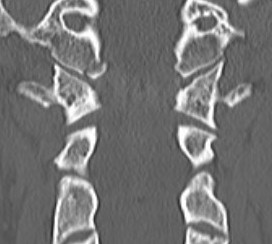

Type II: Occipital condyle fracture involving base of skull

Type III: Inferomedial alar ligament avulsion

Type II: Basal skull involvement